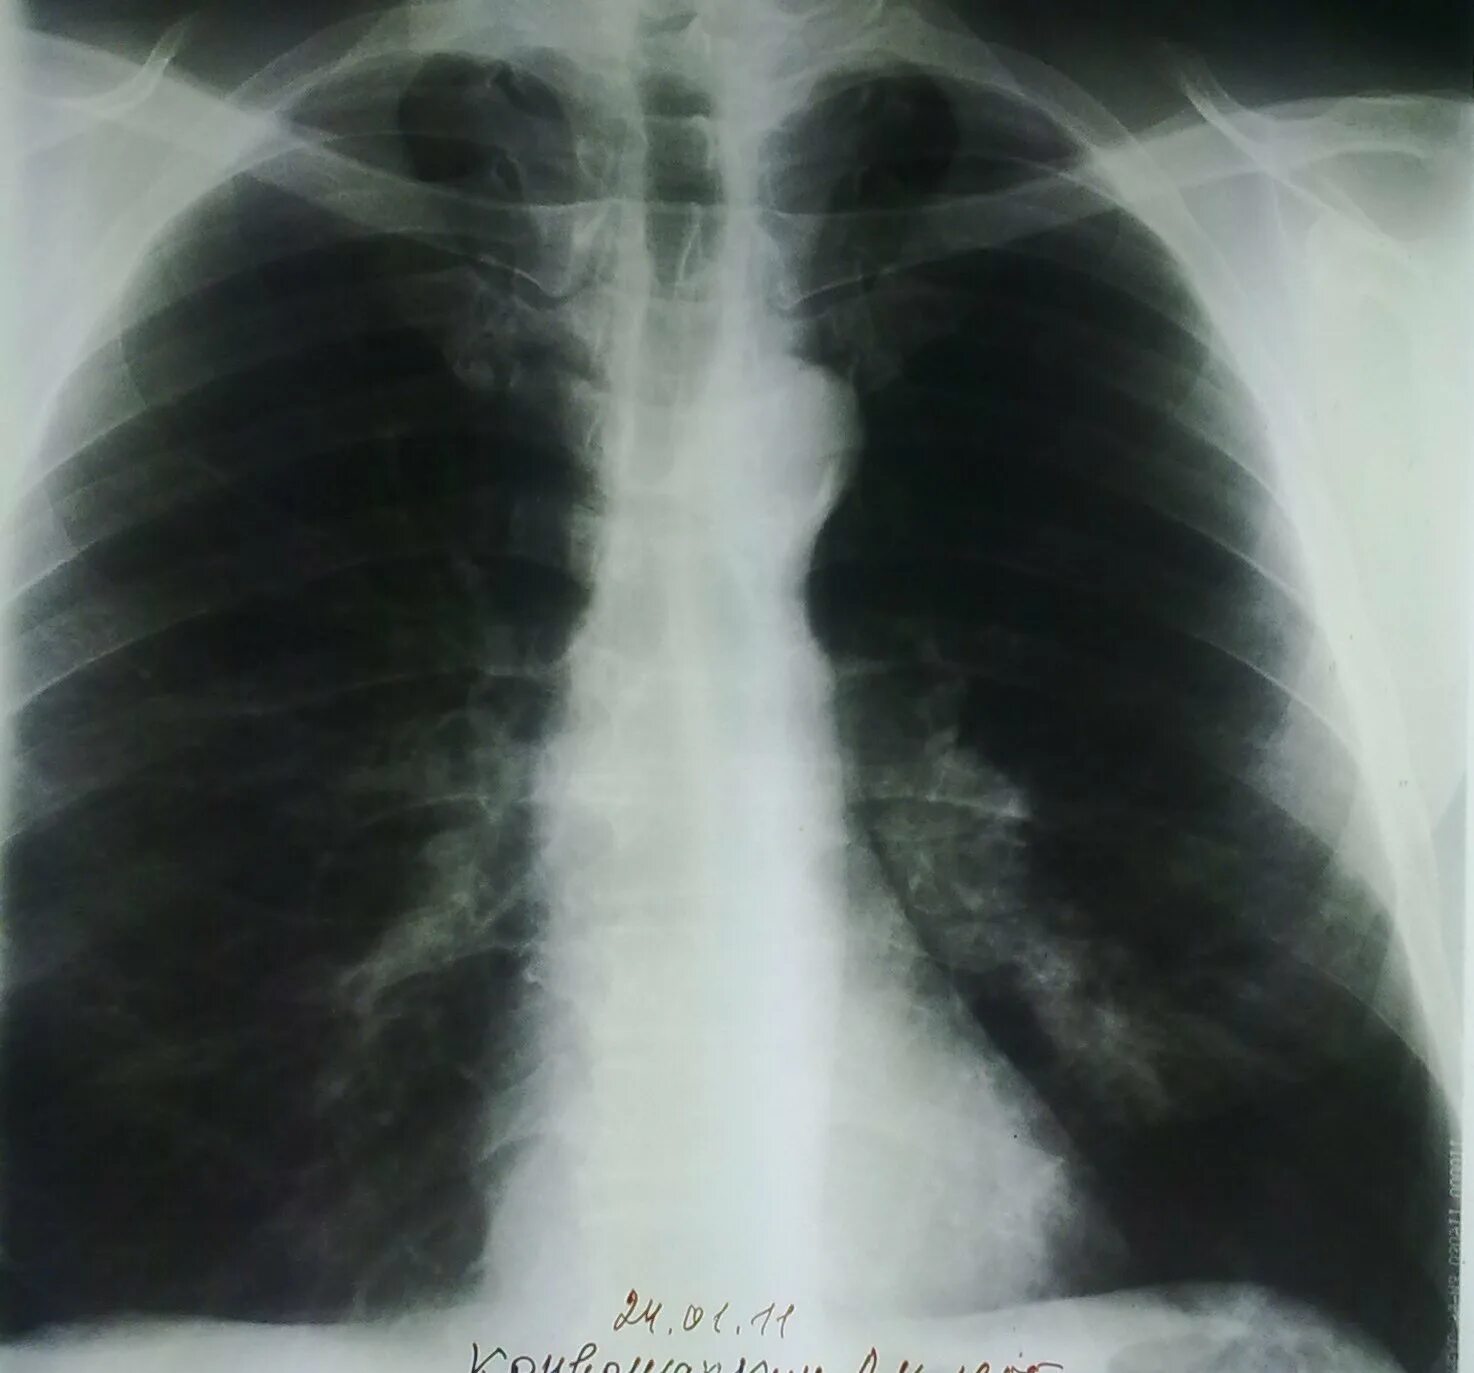

Пневмосклероз легких прогноз